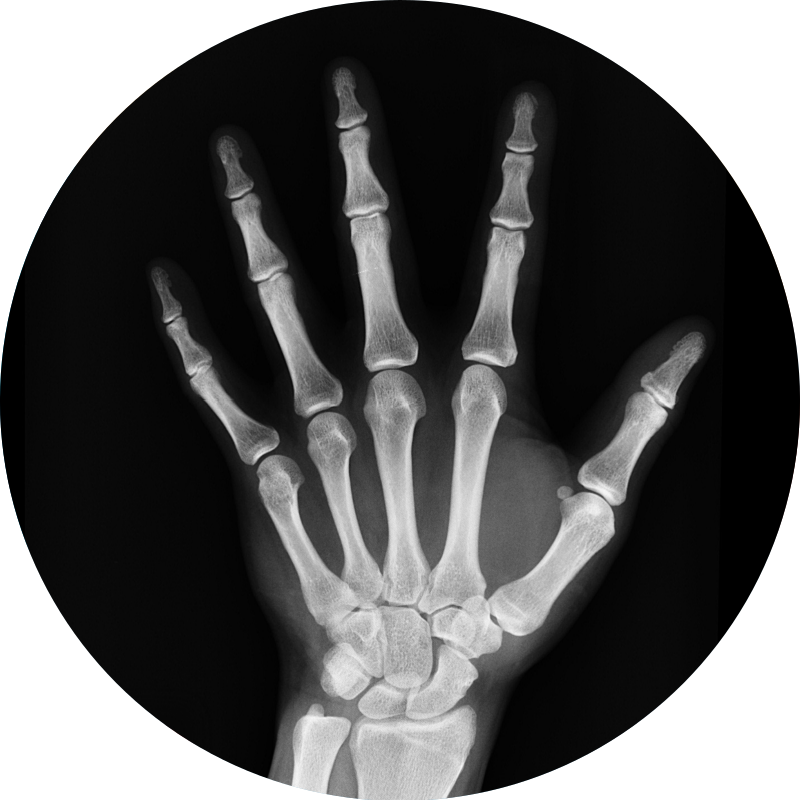

엑스레이

(

X-ray

)

엑스레이(X-ray)는 X선을 인체에 투과시켜 만들어진 영상물로

해당 부위의 이상을 확인하는 검사입니다.

근골격계 질환에서 X선검사를 통해

뼈와 주변 연부조직의 구조이상 유무를 확인할 수 있습니다.

특히 류마티스질환에서 이환된 관절의 누적된 변화, 즉 염증의 진행정도를

파악하는데 도움을 줍니다.